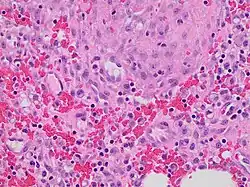

Histopathology of granulation tissue at 11 days after injury, showing fibroblasts, hemorrhage and lymphocytes.

The extracellular matrix of granulation tissue is created and modified by fibroblasts.[5] Initially, it consists of a network of type-III collagen, a weaker form of the structural protein that can be produced rapidly. This is later replaced by the stronger, long-stranded type-I collagen, as evidenced in scar tissue.

The main immune cells active in the tissue are macrophages and neutrophils, although other leukocytes are also present.[6] These work to phagocytize old or damaged tissue, and protect the healing tissue from pathogenic infection. This is necessary both to aid the healing process and to protect against invading pathogens, as the wound often does not have an effective skin barrier to act as a first line of defense.